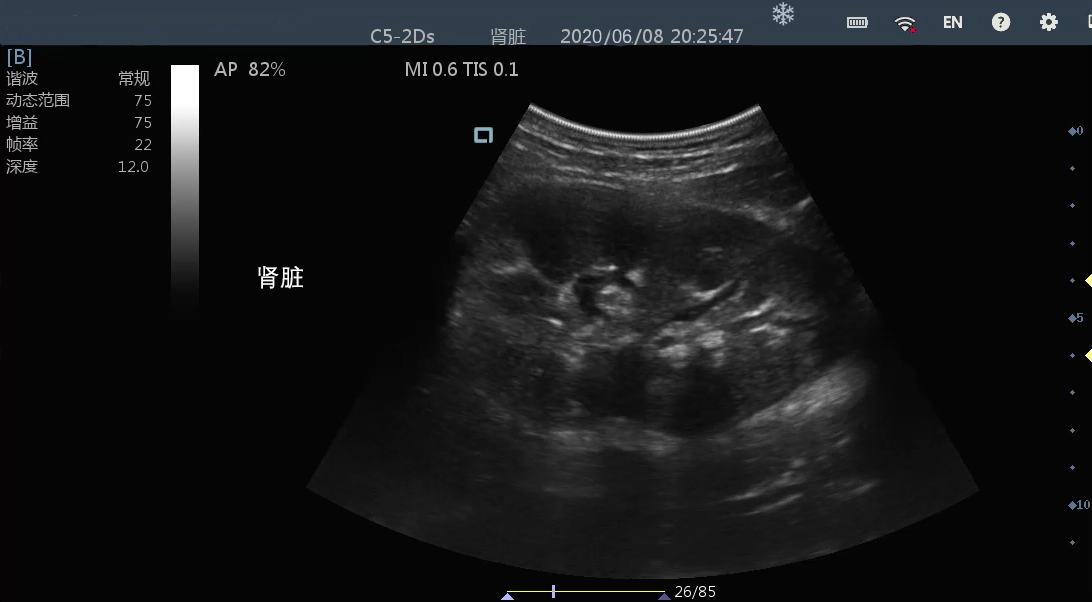

• 微凸

腹部

肾脏

新生儿颅脑

及心脏

小动物等